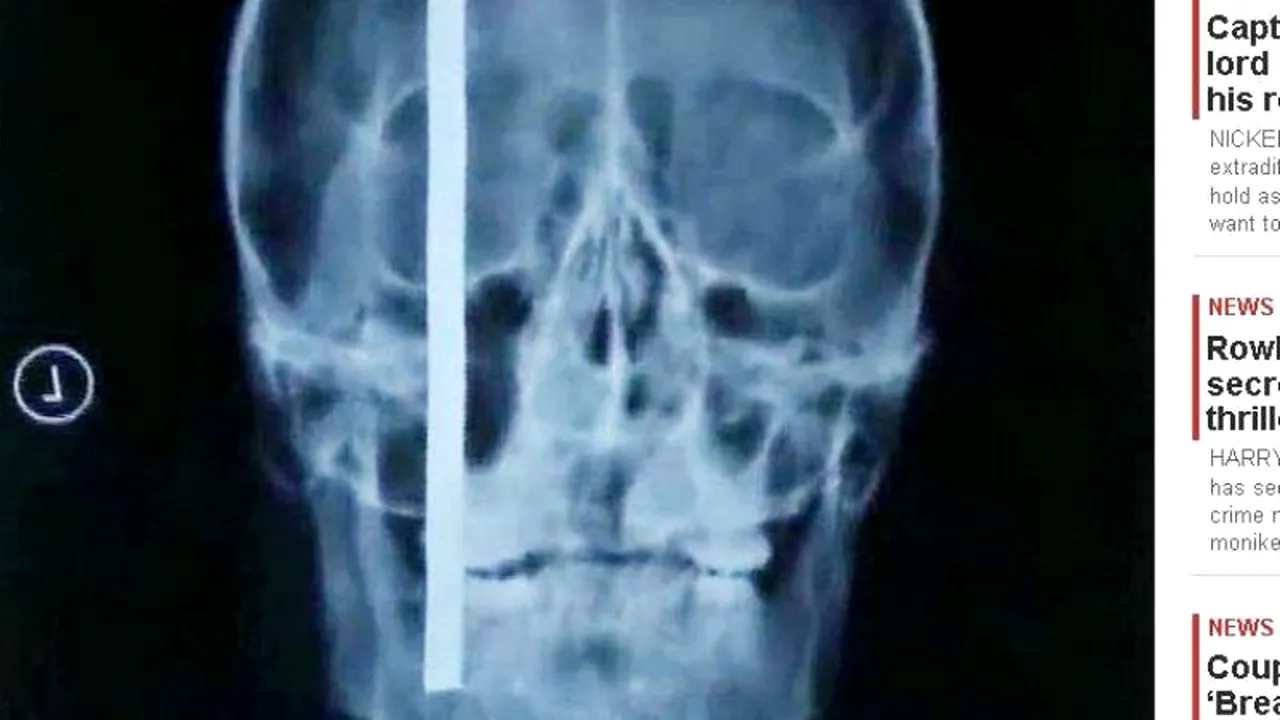

Un chinez a fost operat de urgență la un spital din provincia Shandong după ce o bară de oțel cu o lungime de 45 de centimetri i s-a înfipt în cap, informează The Sun.

Bara de oțel a căzut de la etajul 25 al unei unei clădiri aflate în construcție și i s-a înfipt 20 de centimetri în capul unui muncitor în timp ce acesta stătea de vorbă cu un coleg.

FOTO: The Sun